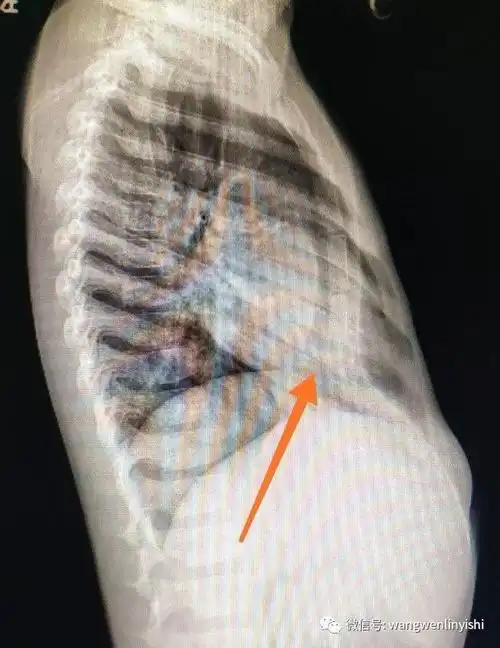

罕见肋骨畸形合并胸廓畸形手术成功